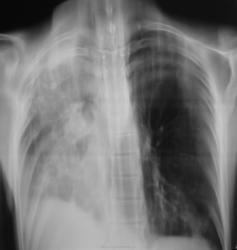

как следствие операции по поводу туберкулеза легких. Если сейчас выделяет МБТ, то следует расценивать как реактивацию туберкулезного процесса. Думаю, что вспышка туберкулёза  есть.

По рентгенограммам фиброторакс как бы неполный, однако, на представленных томограммах правый главный бронх в виде культи, но нечётко видимой. И металл. зажимы в срезы не попали. Там точно всё удалено?

Левое лёгкое с патологией и в нижней доле и в верхней.

Согласно документам - пульмонэктомия.

Ну пульмонэктомия-значит пульмон эктомия , ничего нового.Только надо иметь ввиду грубое смещение органов средостения и медиастинальная грыжа.

С медиастинальными грыжами понятно. А что ещё светится на месте удалённого лёгкого? При фибротораксе такого не может быть. Когда была операция? И клиники хоть ложку надо.

Следующий случай.